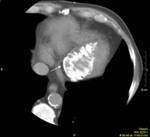

Results: Twenty-two cardiac masses were successfully detected and their characteristics adequately delineated, including eight myxomas, one angiosarcoma, one ventricular lymphoma, one endocardiac metastasis, one epicardiac paraganglioma, and 10 cases of intracardiac thrombi.

Conclusion: CT and MRI are noninvasive imaging modalities which can delineate cardiac tumors and masses and provide essential information for adequate diagnosis, staging and treatment planning. Compared to cardiac ultrasound, CT and MRI are superior in preoperative planning.